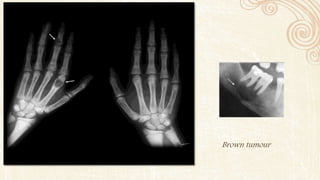

Radigraphically observable changes are seen in 1 out of 5 patients

Earliest changes are subtle erosions of the bone from the periosteal

surfaces of the phalanges from hand

 Brown tumor occur late in the disease .

Brown tumour